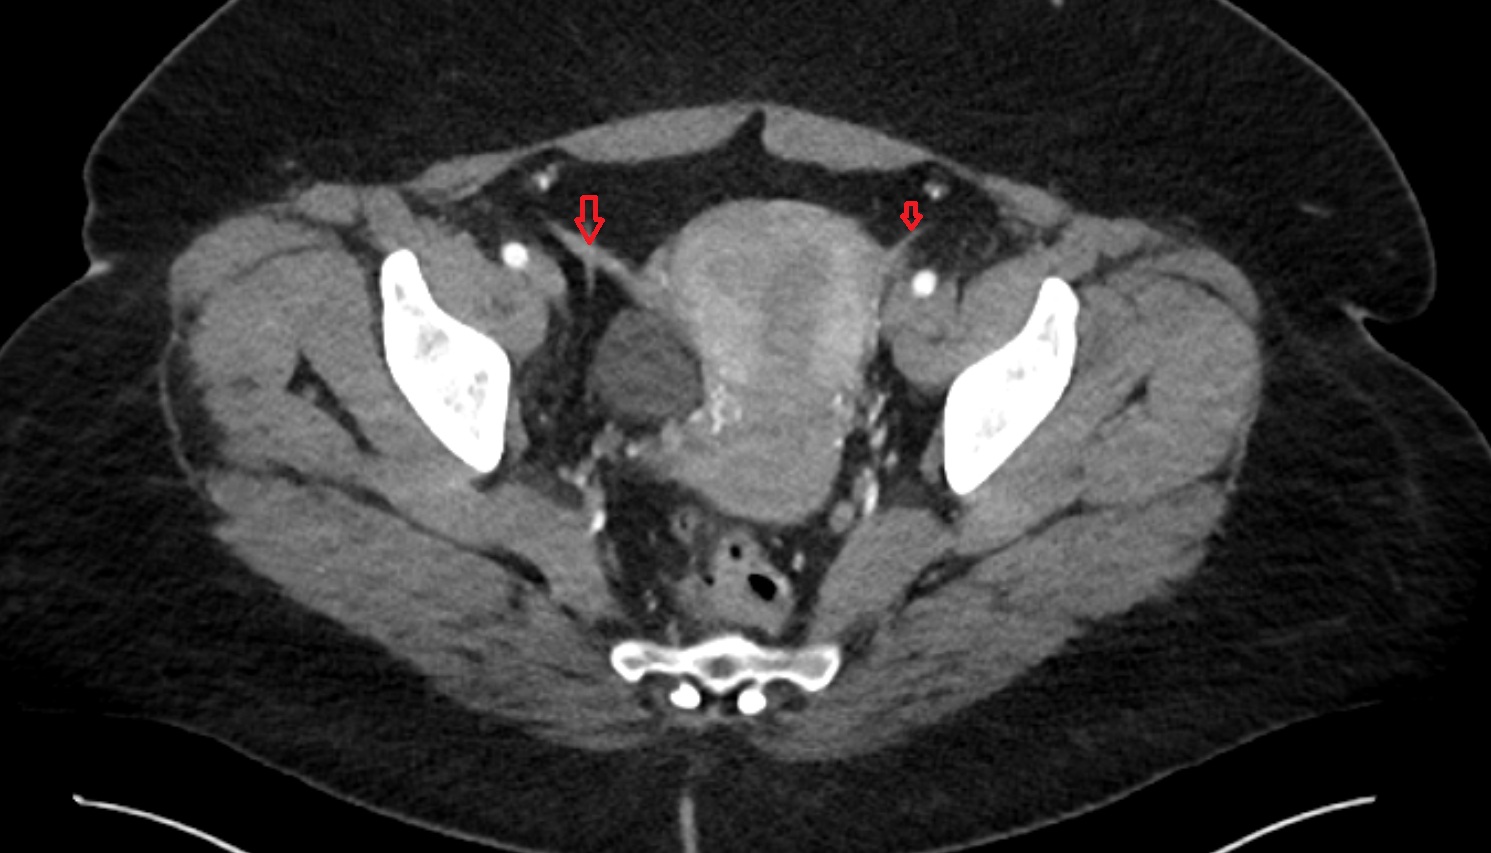

- Intermediate lacunar external iliac lymph nodes

- External iliac lymph nodes

- Obturator lymph nodes